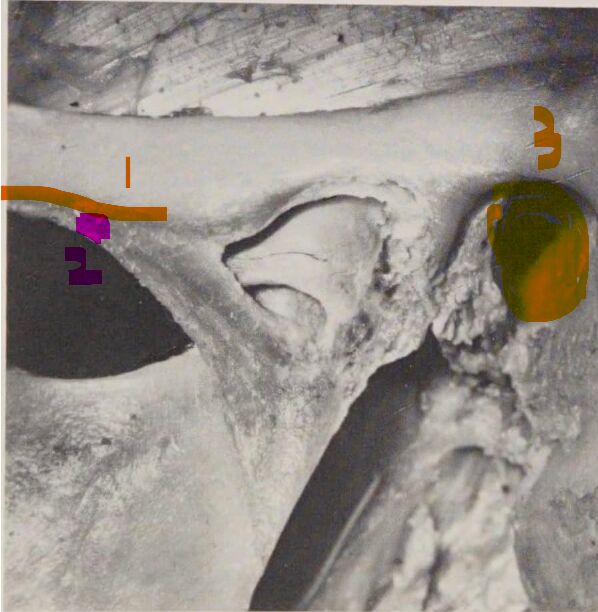

13 顳顎關節韌帶附著於顱底之圖示,若編號 3 之處代表為外耳道,則下列敘述何者為非?

(A)編號 1 處為外斜韌帶(outer oblique ligament)

(B)編號 1 附連至關節結節(articular tubercle)與顴弓(zygomatic arch)

(C)編號 2 為內側水平韌帶(inner horizontal ligament)

(D)編號 2 將附連至關節結節(articular tubercle)與下顎小舌(mandibular lingula)

編號 1 - 外斜Outer oblique li - 附連至關節結節(articular tubercle)與顴弓(zygomatic arch)

編號 2 - 內側水平 Inner horizontal li. - 將附連至關節結節(articular tubercle)與髁的外側極和關節盤的後部